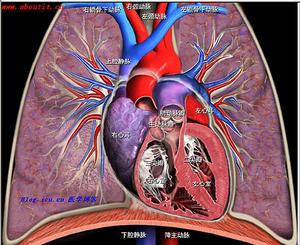

血管造影顯示:管腔不規則,管腔狹窄與閉塞,管腔呈瘤樣擴張。心血管疾病的超聲診斷外,影像學中亦能發現血管壁增厚,管腔狹窄等病變。影像學中X線體層檢查亦能發現血管壁增厚,管腔狹窄等病變。影像學中磁共振檢查亦能發現血管壁增厚,管腔狹窄等病變。